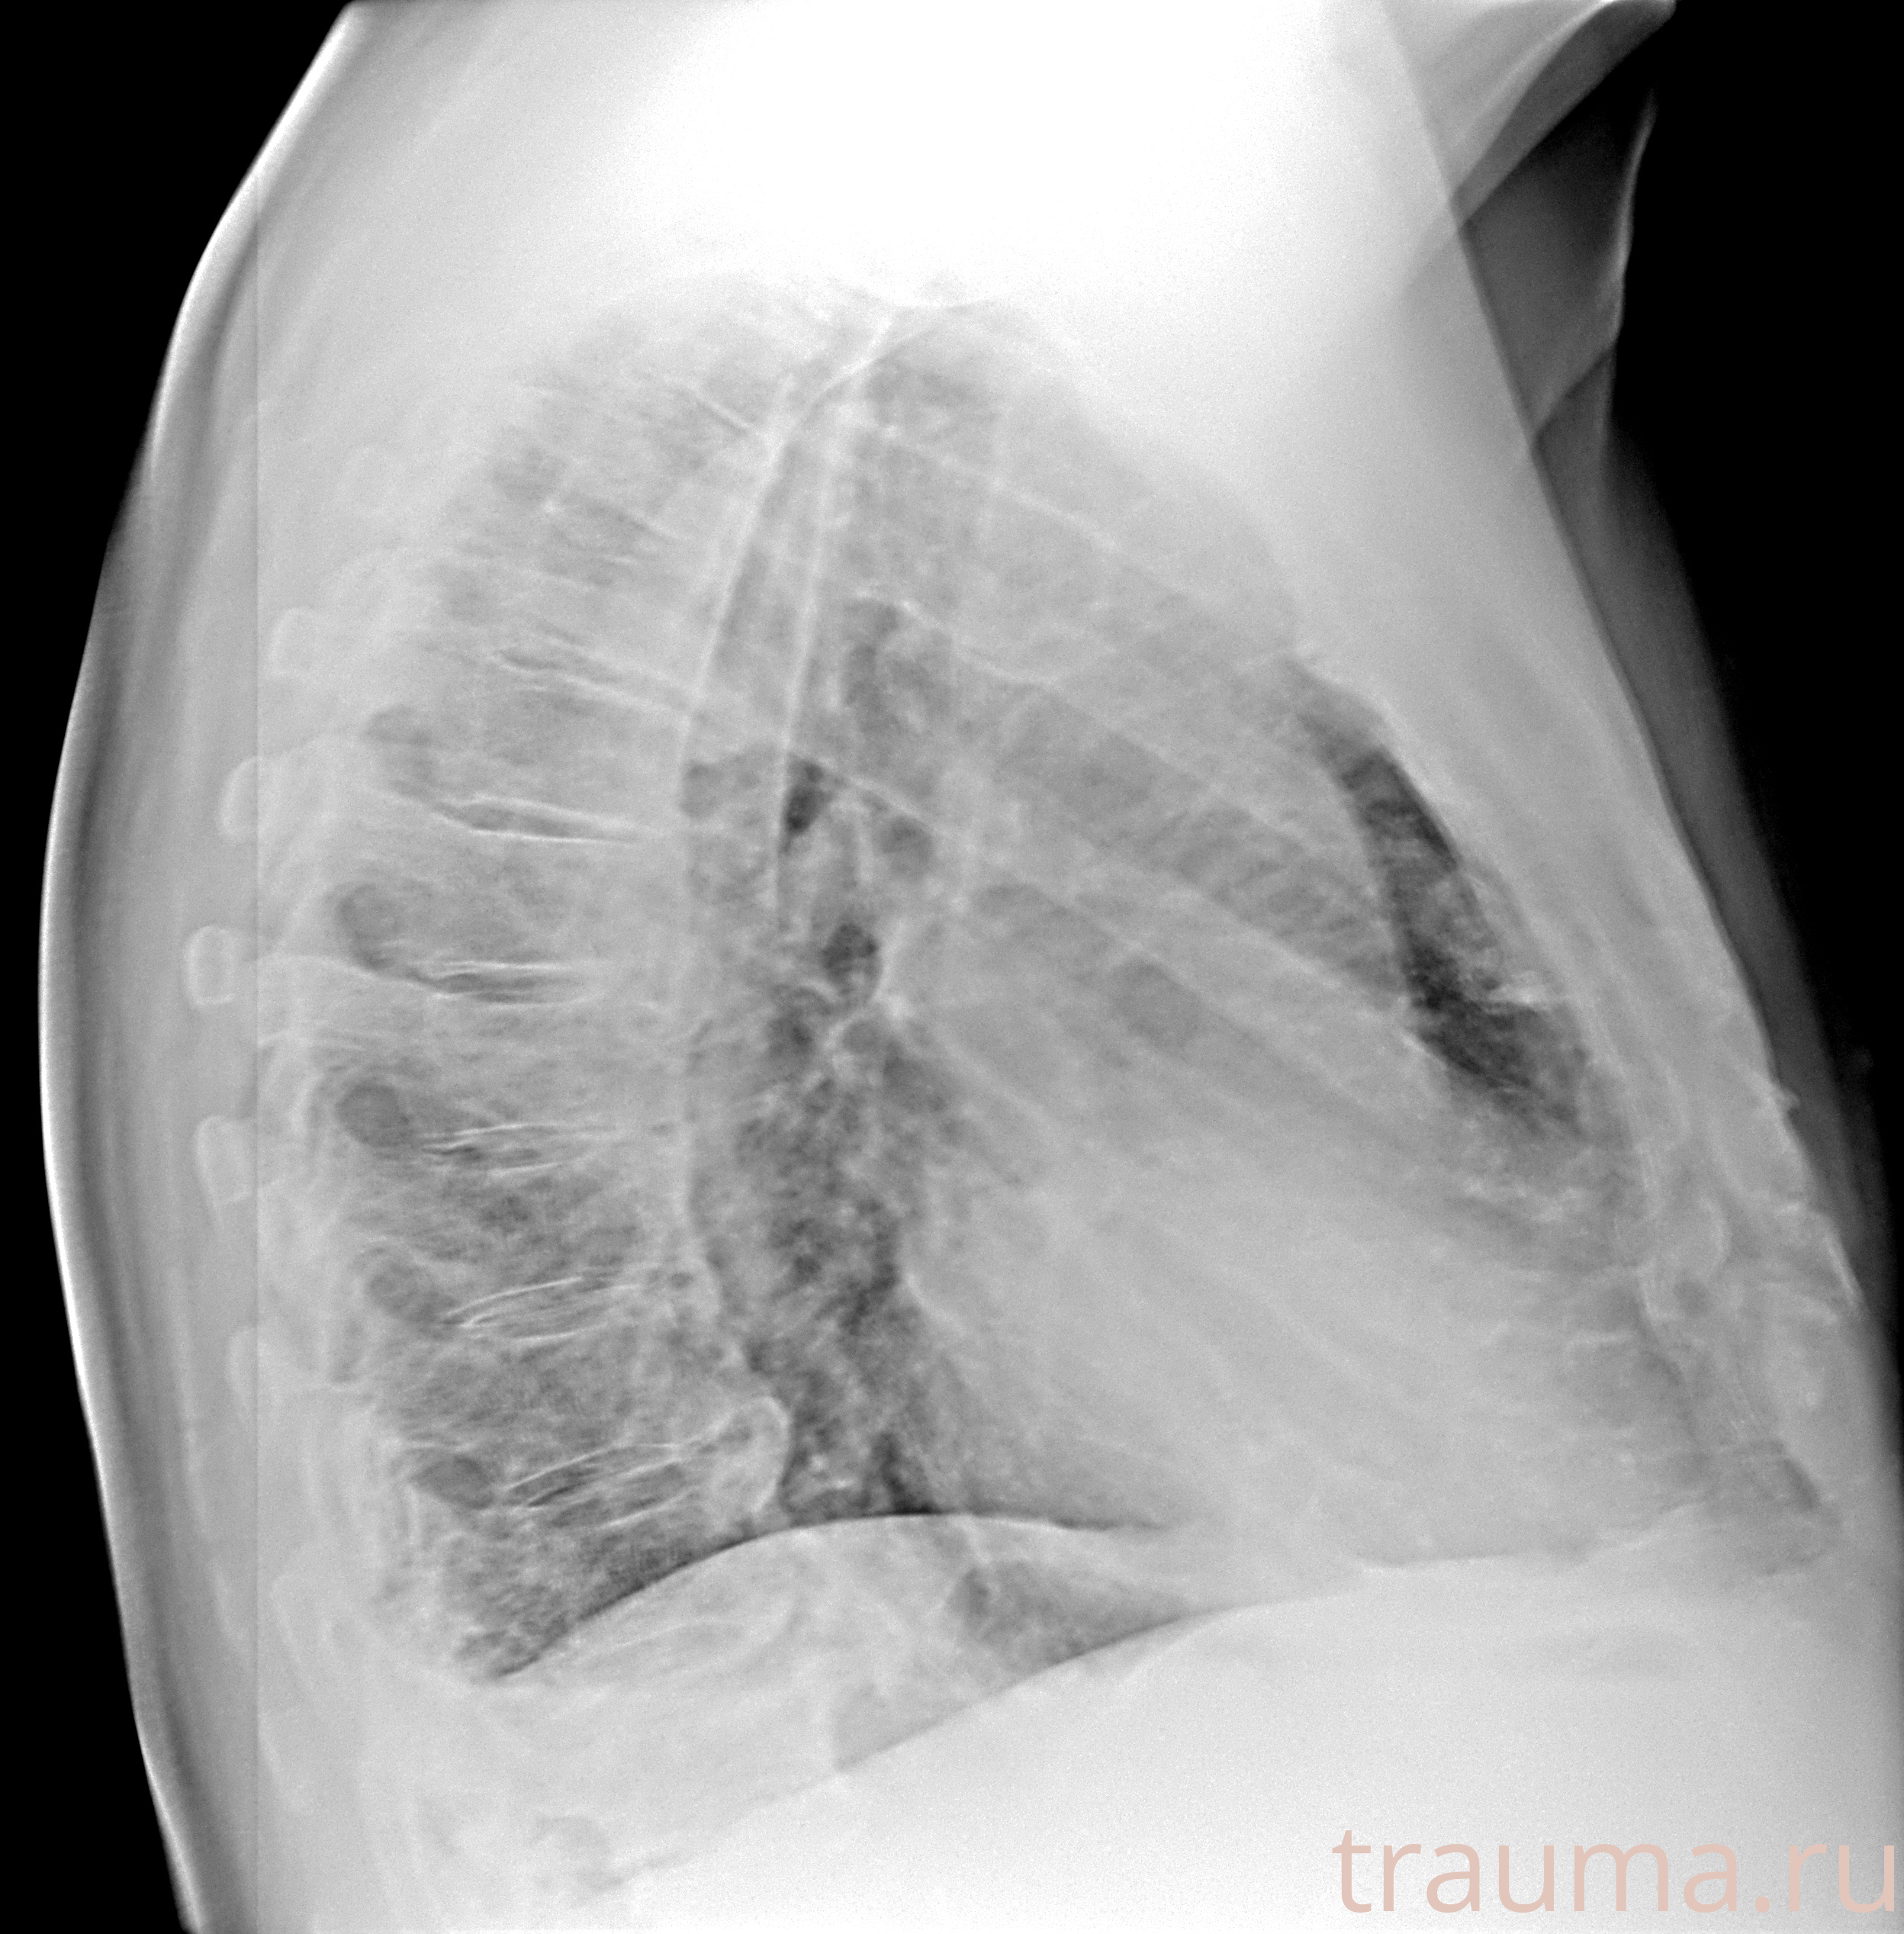

Рентгенограммы

Рентген на дому: по вашему адресу приезжает врач-рентгенолог, травматолог-ортопед с мобильным рентгеновским аппаратом, проводит диагностику травмы или заболевания, делает необходимые рентгенограммы, дает рекомендации по дальнейшему лечению. Получить качественные снимки в домашних условиях возможно благодаря уникальной методике, разработанной МосРентген Центром для института  Склифосовского

Яркость: 1   Контраст: 1   Инвертировать: 0 Увеличение: 1

Перетаскивайте мышь вверх/вниз для контраста, влево/право для яркости. Прокрутка колесом изменяет масштаб. Нажмите Сбросить для возврата к исходному изображению. При увеличении держите мышь в той области, которую хотите рассмотреть.